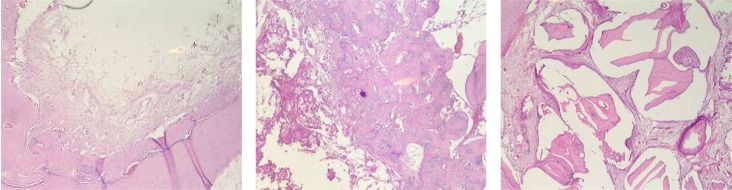

Fig 3.

Hematoxylin and Eosin-stained section of defects. A. Control, new bone formation is observed on the border and fibrous connective tissue is discernible in the center of the defect. B. β-TCP, abundant new bone formation is observed around β-TCP particles. C. ABB, residual particles are seen in the defect (original magnification ×40).